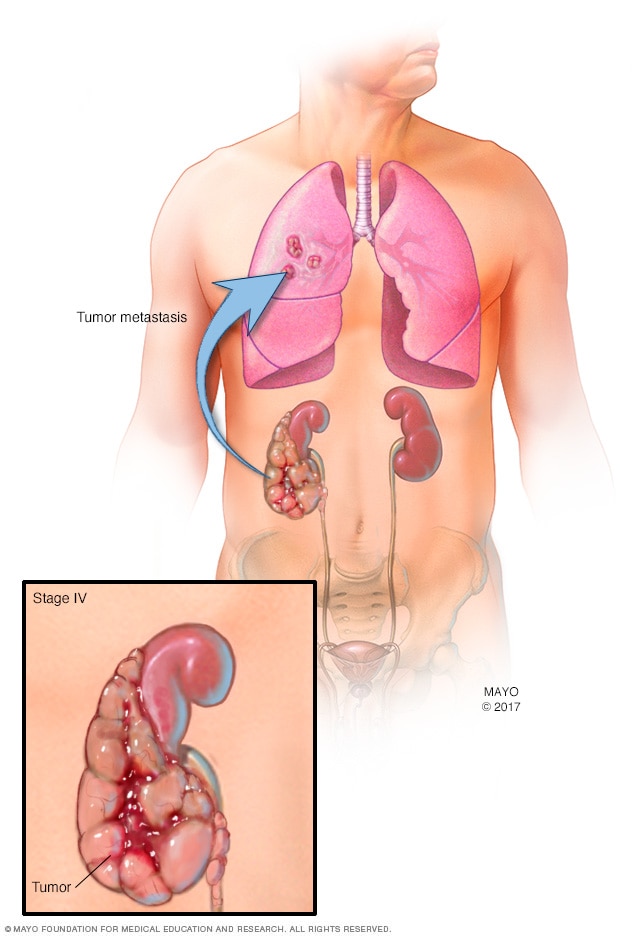

Stage 4 kidney cancer

A stage 4 kidney cancer may mean that the tumor has grown beyond the kidney. It also may mean that the cancer has spread to other parts of the body, such as the bones, liver or lungs.

The cancer cells form a mass called a tumor. The tumor can grow to invade and destroy healthy body tissue. In time, cancer cells can break away and spread to other parts of the body. When cancer spreads, it's called metastatic cancer.